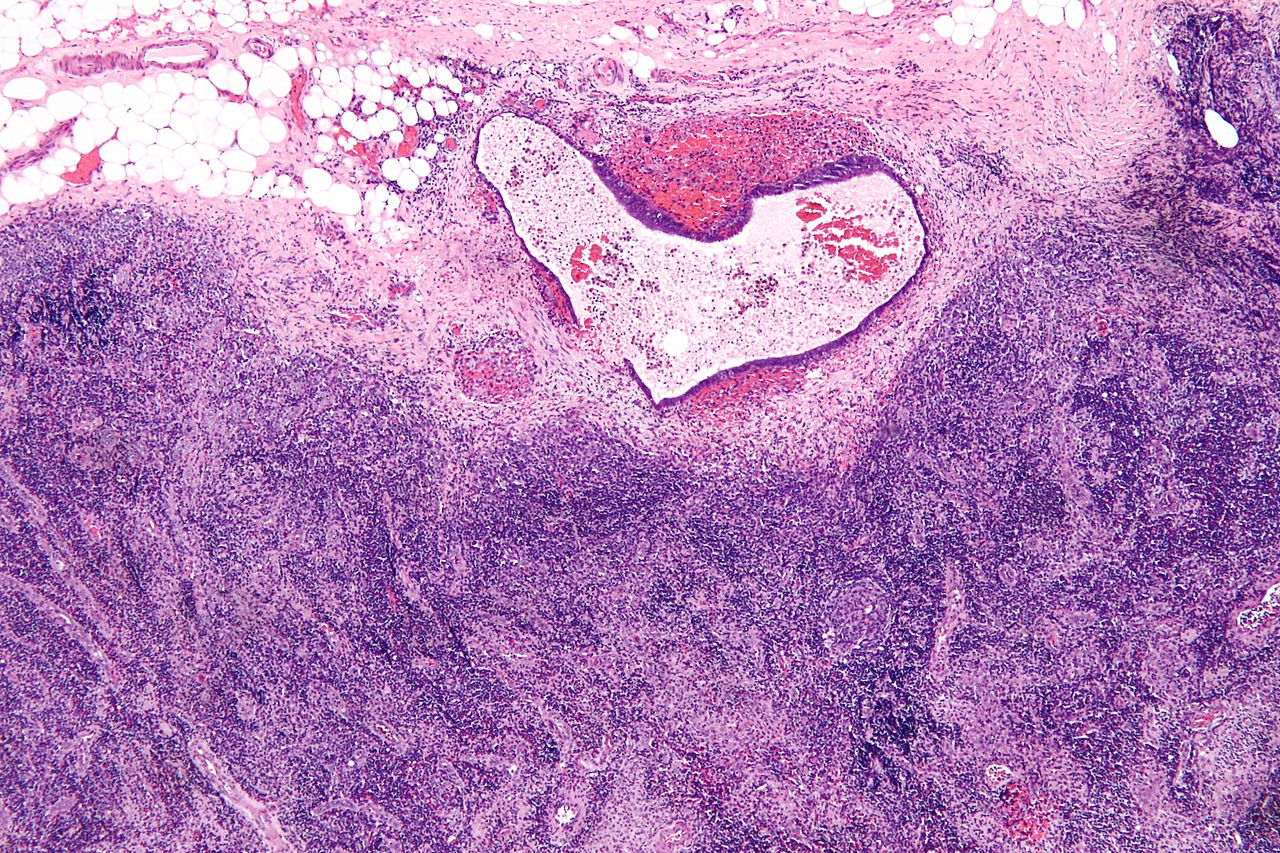

Endometrioza apare din cauza aparitiei de tesut tip endometrial in partea exterioara a cavitatii uterine. Se stie ca acest tesut endometrial are rolul de a captusi cavitatea uterului si astfel in momentul in care o femeie sufera de aceasta boala ginecologica tesutul este gasit in locatii extrauterine – lucru ce nu mai este normal din punct de vedere functional.

Tesuturile de tip ectopic anormale pot sa apara in zonele alaturate organelor ce tin de aparatul genital al femeii, ca de exemplu in locurile adiacente ovarelor, vezicii urinare, ligamentelor uterocostale si altele. In anumite cazuri localizarea lor poate fi relativ ciudata cum sunt plamanii, tesutul inimii sau sistemul nervos central.